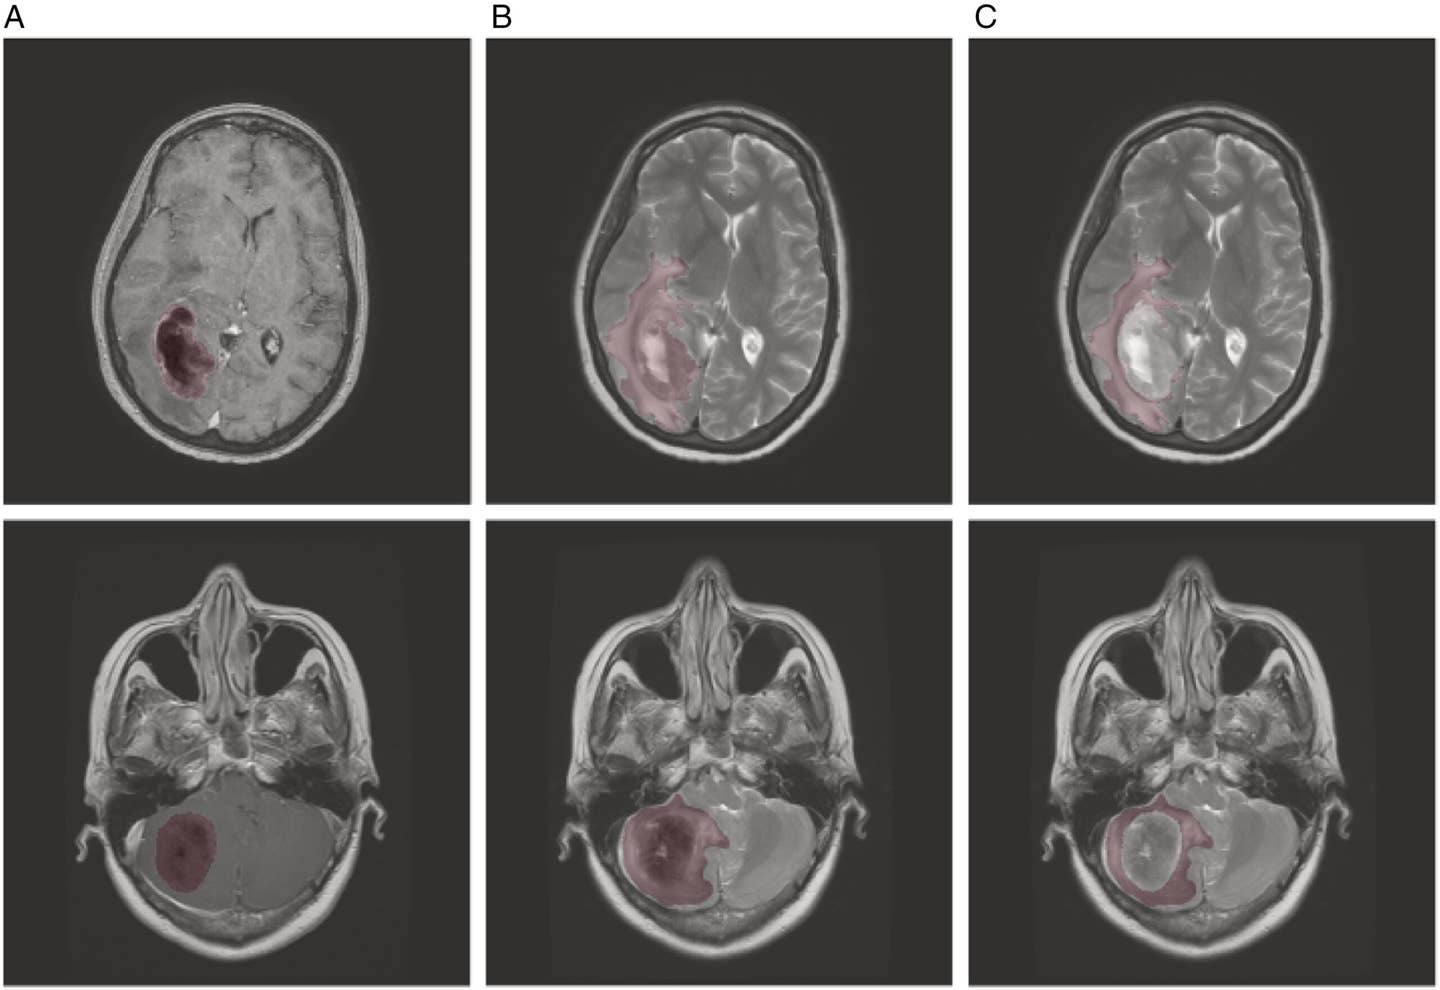

Published in the journal, Neuro-Oncology Advances, researchers have developed a machine learning model that can predict brain metastasis invasion patterns (BMIP) using features extracted from MRI scans. This innovation holds the potential to replace invasive diagnostic procedures with a more patient-friendly alternative.

The model’s success stems from its ability to analyze nuanced features in MRI scans. Preoperative scans were processed using advanced normalization tools to align data from different MRI machines, ensuring consistency. Researchers utilized T2-weighted (T2W) and contrast-enhanced T1-weighted (T1WC+) sequences, key for delineating tumor boundaries and associated edema—a hallmark of tumor invasion.

Manual segmentation of tumors and surrounding edema formed the foundation of the dataset. Expert neuroradiologists refined these initial contours, ensuring precision by removing imaging artifacts and accounting for leptomeningeal invasion. Computational algorithms then generated additional regions of interest, isolating tumor and edema zones. These steps enabled the model to capture subtle features indicative of cancer spread.